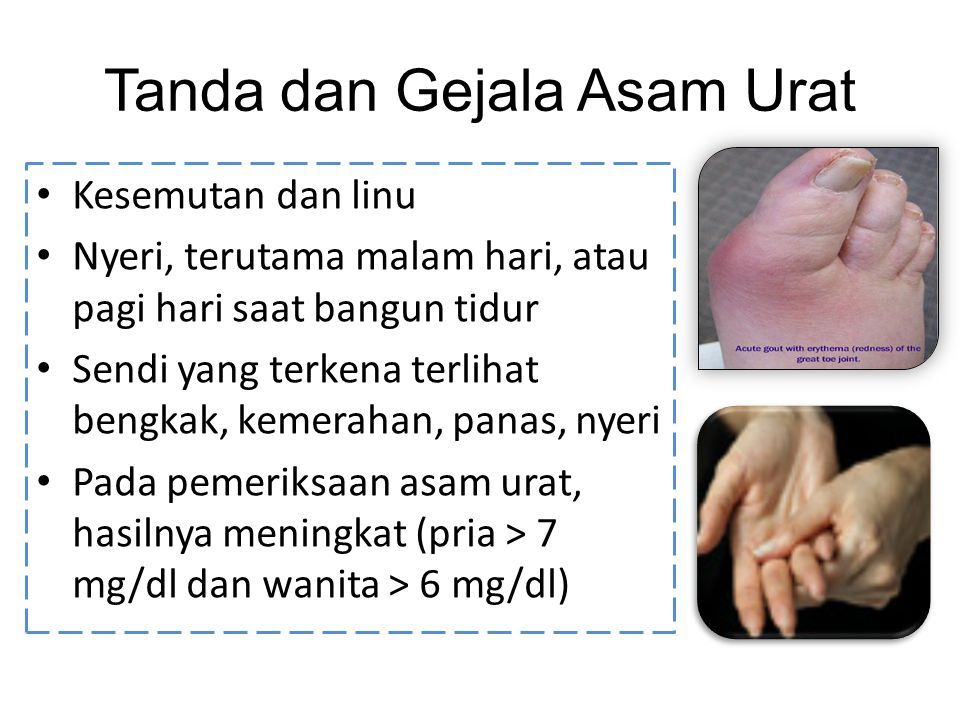

Asam Urat Dr Sukma Susanti S Ked Prolanis Puskesmas Cabenge Ppt Download

Asam Urat Dr Sukma Susanti S Ked Prolanis Puskesmas Cabenge Ppt Download

Asam Urat Dr Sukma Susanti S Ked Prolanis Puskesmas Cabenge Ppt Download

Asam Urat Dr Sukma Susanti S Ked Prolanis Puskesmas Cabenge Ppt Download